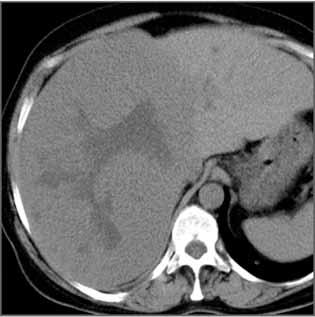

Rycina 38.40. Rycina 38.41.